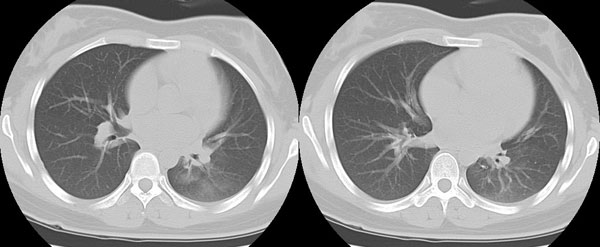

女性,25岁。反复咯血3年,再咯10天。外院x线胸片示:肺炎?支扩?

ct所见:左肺下叶基底段见大片状毛玻璃样改变,其内可见扩张细支气管。

ct诊断:考虑支气管扩张合并感染.

ct所见:左肺下叶基底段见大片状毛玻璃样改变,其内可见扩张细支气管及血管纹理影。后接正常描述。

ct诊断:左肺下叶支气管扩张伴出血。

胸部ct平扫所见:胸廓两侧欠对称,左侧略小,胸壁骨质结构完整。左肺下叶后、外基底段

见大片状毛玻璃样淡薄影,边缘渐淡,其内可见多个环形小囊状影。余肺野清晰,

肺纹理规则,气管支气管通畅,内壁光滑。心脏、大血管大小、形态、密度未见

明显异常,胸膜不厚、光滑,纵隔内未见明显肿大淋巴结。

诊断意见:左肺下叶大片状毛玻璃样淡薄影考虑支气管扩张伴出血。